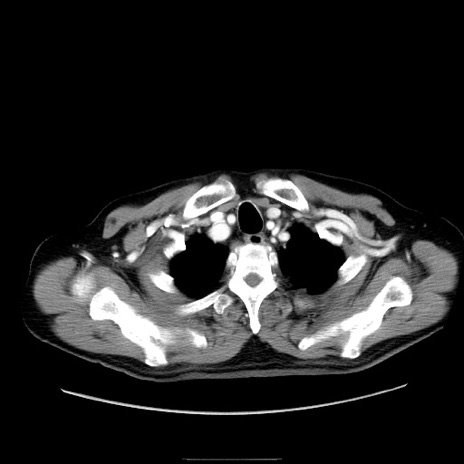

症例30(横断像)

【症例】80歳代男性

【主訴】臍周囲痛

【現病歴】約6時間前から臍下部痛が出現。次第に腹部膨隆・背部痛も生じてきたため来院。背部痛の場所は変化しない。

【身体所見】意識清明、BT 36.3℃、BP  131/87mmHg、P 87bpm、SpO2 100%(RA)、臍周囲自発痛・圧痛あり、反跳痛なし、自発痛部位に一致して板状硬あり、腹部膨隆、腸雑音減弱、CVA tenderness両側陰性。

【データ】WBC 19600、CRP 0.33